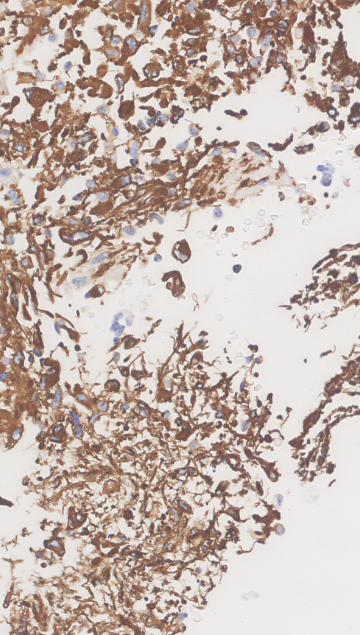

3.5.2 Data

The data presented in this study have been acquired from digital images of immunohistochemistry stainings that were performed on archival tissue obtained from the neurobiobank of the Division of Neuropathology and Neurochemistry at the Medical University of Vienna. Stainings have been performed according to standard procedures (citep \@BBN(Guo et al., 2024; Schwaiger et al., 2023)). Figure 11 (a)-(c) shows a tumour biopsy of a gliosarcoma patient stained for the astrocyte marker GFAP (brown signal, cytoplasmic localization) and counterstained with Hematoxylin (blue signal, nuclear localization). Figure 3 (d)-(e) shows fetal cerebellar tissue stained for the epigenetic mark H3K27me3 (brown signal, nuclear localization) and counterstained with Hematoxylin (blue signal, nuclear localization). The stained sections have been digitalized on a NanoZoomer 2.0-HT digital slide scanner C9600 (Hamamatsu Photonics, Hamamatsu, Japan). The corresponding software NPD.Viewer2 was used to export the scanned images to tiff files. Here, we performed individual scans of a selected imaging area with different numbers of focus points. We chose either 1, 3 or 9 focus points while not changing the spatial settings for the selected field of interest. The image with 9 focus points, allowing the highest resolution, serves as the reference image.

Figure 11: Data acquired with a slide scanner and 9 (a)(d), 3 (b)(e) and 1 (c)(f) focus points. The image with 999 focus points serves as a reference here. PSNR and SSIM misjudge the tiny spatial misalignment and therefore favor the blurry images with 1 focus point. LPIPS is able to ignore these spatial misalignments.

FR-IQA mismatches

Although the spatial settings for the selected scan area of interest were not changed during the experiment, the physical performance of the scanner showed slight spatial deviations of the selected area between individual scans and thus does not allow for high spatial accuracy during re-scanning processes. PSNR and SSIM fail to correctly assess the images in Figure 11 as they are very sensitive to that kind of misalignments. Whereas clearly the scan with 3 focus points corresponds much better to the reference as the blurred scan with 1 focus point, see (b) and (e) versus (c) and (f), both measures incorrectly judge the blurred scan as better. This wrong judgement due to a tiny spatial change is very problematic in the respective framework, as it is impossible to guarantee completely exact spatial alignment, even if no other settings had been changed during the scanning process. LPIPS is able to correctly judge the rank of quality here.